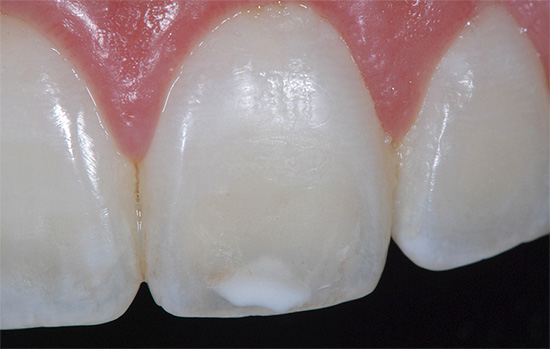

É importante entender que, em casa, é possível tratar a cárie apenas no primeiro estágio inicial, quando uma lesão dentária parece um ponto brilhante. Nesta fase, com a ajuda de medidas e meios especiais, é completamente possível interromper a destruição adicional do esmalte e, além disso, garantir a introdução de componentes minerais nele para restaurar o estado saudável inicial.

- A cárie em si se parece com um ponto branco liso.

- Não há pontos e traços pretos (os últimos são característicos de cárie de fissura).

Se houver um orifício no esmalte (cavidade), definitivamente não será possível curar um dente sem obtê-lo. Em muitos casos, essas lesões de cárie que só podem ser tratadas por um dentista se apresentam como manchas marrons ou pretas distintas.